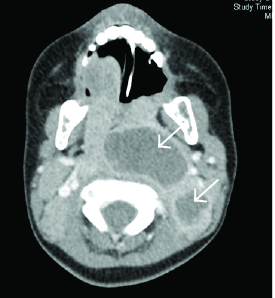

CT of the neck with IV contrast is the best study to identify abscesses in the retropharyngeal space. It can demonstrate extension of an abscess into contiguous spaces in the neck or chest and help differentiate between abscess and cellulitis. CT also can help identify the position of critical vessels in the neck when planning surgical intervention. (See Figure 4.)

Figure 4. CT Neck with Contrast Reveals Two Retropharyngeal Abscesses in an Intubated Patient |

Image courtesy of Derya Caglar, MD. |